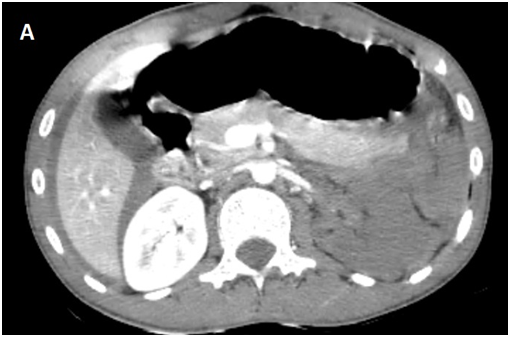

Whole body CT Scanner was performed 5hours after the accident Figure 1, which revealed a laceration fracture of the spleen responsible for a low abundant intraperitoneal hematoma, associated with left renal ischemia due to a sub intimal damage on the left renal artery wall, with formation of a secondary obstructive thrombus, in addition to a left peri-renal hematoma of 16mm, without parenchymal lesions or extravasation of contrast, otherwise ; left vein, the right kidney and his pedicle were intact.

Figure 1A Contrast enhanced CT abdominal scan.

laceration fracture of the spleen responsible for a low abundant intraperitoneal hematoma, associated with left renal ischemia due to a sub intimal damage on the left renal artery wall, with formation of a secondary obstructive thrombus, in addition to a left peri-renal hematoma of 16mm, without parenchymal lesions or extravasation of contrast, otherwise ; left vein, the right kidney and his pedicle were intact.